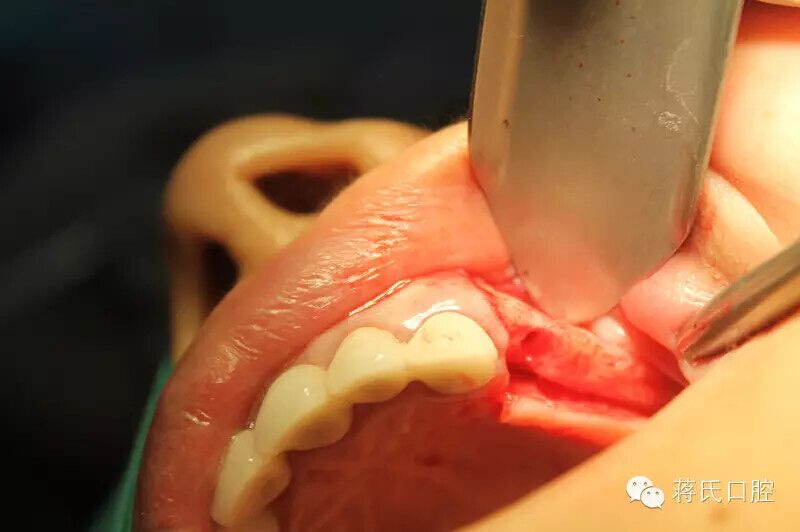

10.左側(cè)切開后

11.第一洞制備完成

12.左側(cè)外提升過程